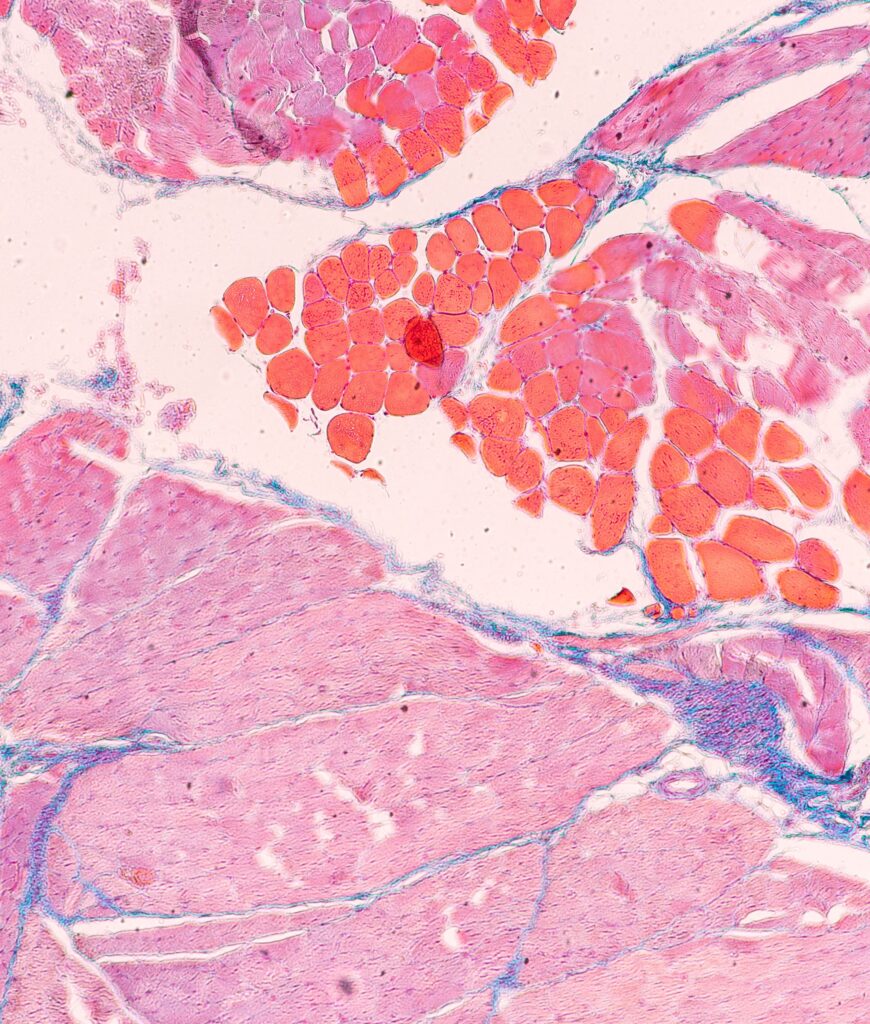

Le muscle squelettique, tissu le plus abondant du corps humain, joue un rôle clé dans la locomotion, la respiration, la thermorégulation et l’homéostasie métabolique. Son altération est impliquée dans de nombreuses pathologies, des maladies neuromusculaires (MNM) comme la dystrophie musculaire de Duchenne (DMD) et l’amyotrophie spinale (SMA), jusqu’à la sarcopénie liée à l’âge et aux maladies chroniques (cancer, diabète). Malgré les avancées en modélisation et en thérapies régénératives, les modèles musculaires humains in vitro ne reproduisent pas la complexité physiologique du muscle natif, notamment son organisation spatiale, sa diversité cellulaire et ses fonctions spécifiques.

Le projet MUSCLOR-oC vise à concevoir une plateforme de muscle humain sur puce de nouvelle génération, reproduisant les propriétés structurelles et contractiles des fibres musculaires et intégrant deux interfaces majeures: la jonction neuromusculaire (JNM) et la jonction myotendineuse (JMT). Ces structures, essentielles à l’innervation et à la transmission de la force, sont fréquemment altérées dans les MNM. Or, à ce jour, aucun modèle ne permet leur coexistence fonctionnelle dans un même tissu in vitro, limitant leur pertinence translationnelle.

Les données préliminaires des partenaires démontrent la faisabilité et la performance des tissus musculaires 3D dérivés de cellules souches musculaires primaires et d’hiPSC. Ces constructions présentent des myofibres matures, une activité contractile et des signatures pathologiques qui récapitulent les phénotypes des maladies. D’autres innovations technologiques incluent des puces personnalisées à base de PDMS conçues pour la modularité et le suivi de la force en temps réel, ainsi que de nouveaux biomatériaux qui améliorent la différenciation myogénique et l’organisation structurelle. L’intégration avec des approches de pointe de séquençage de l’ARN sur noyau unique permet une analyse domaine-spécifique de haute résolution.